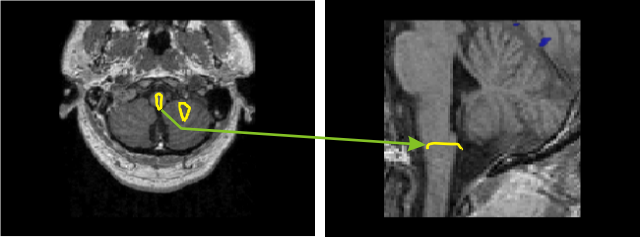

Brainstem and cerebellum

Statistical parametric map for left arm stimulation from 30 single trials (comparison to the pre-stimulus baseline, integrated over 200ms window, yellow contour P < 0.00005). Activity is seen in the gracile and cuneate nuclei and in the gracile lobe of the cerebellum, contralateral to stimulated arm. On the right sagittal MRI, the contour (P < 0.00005) is at the level of the gracile and cuneate nucleus.